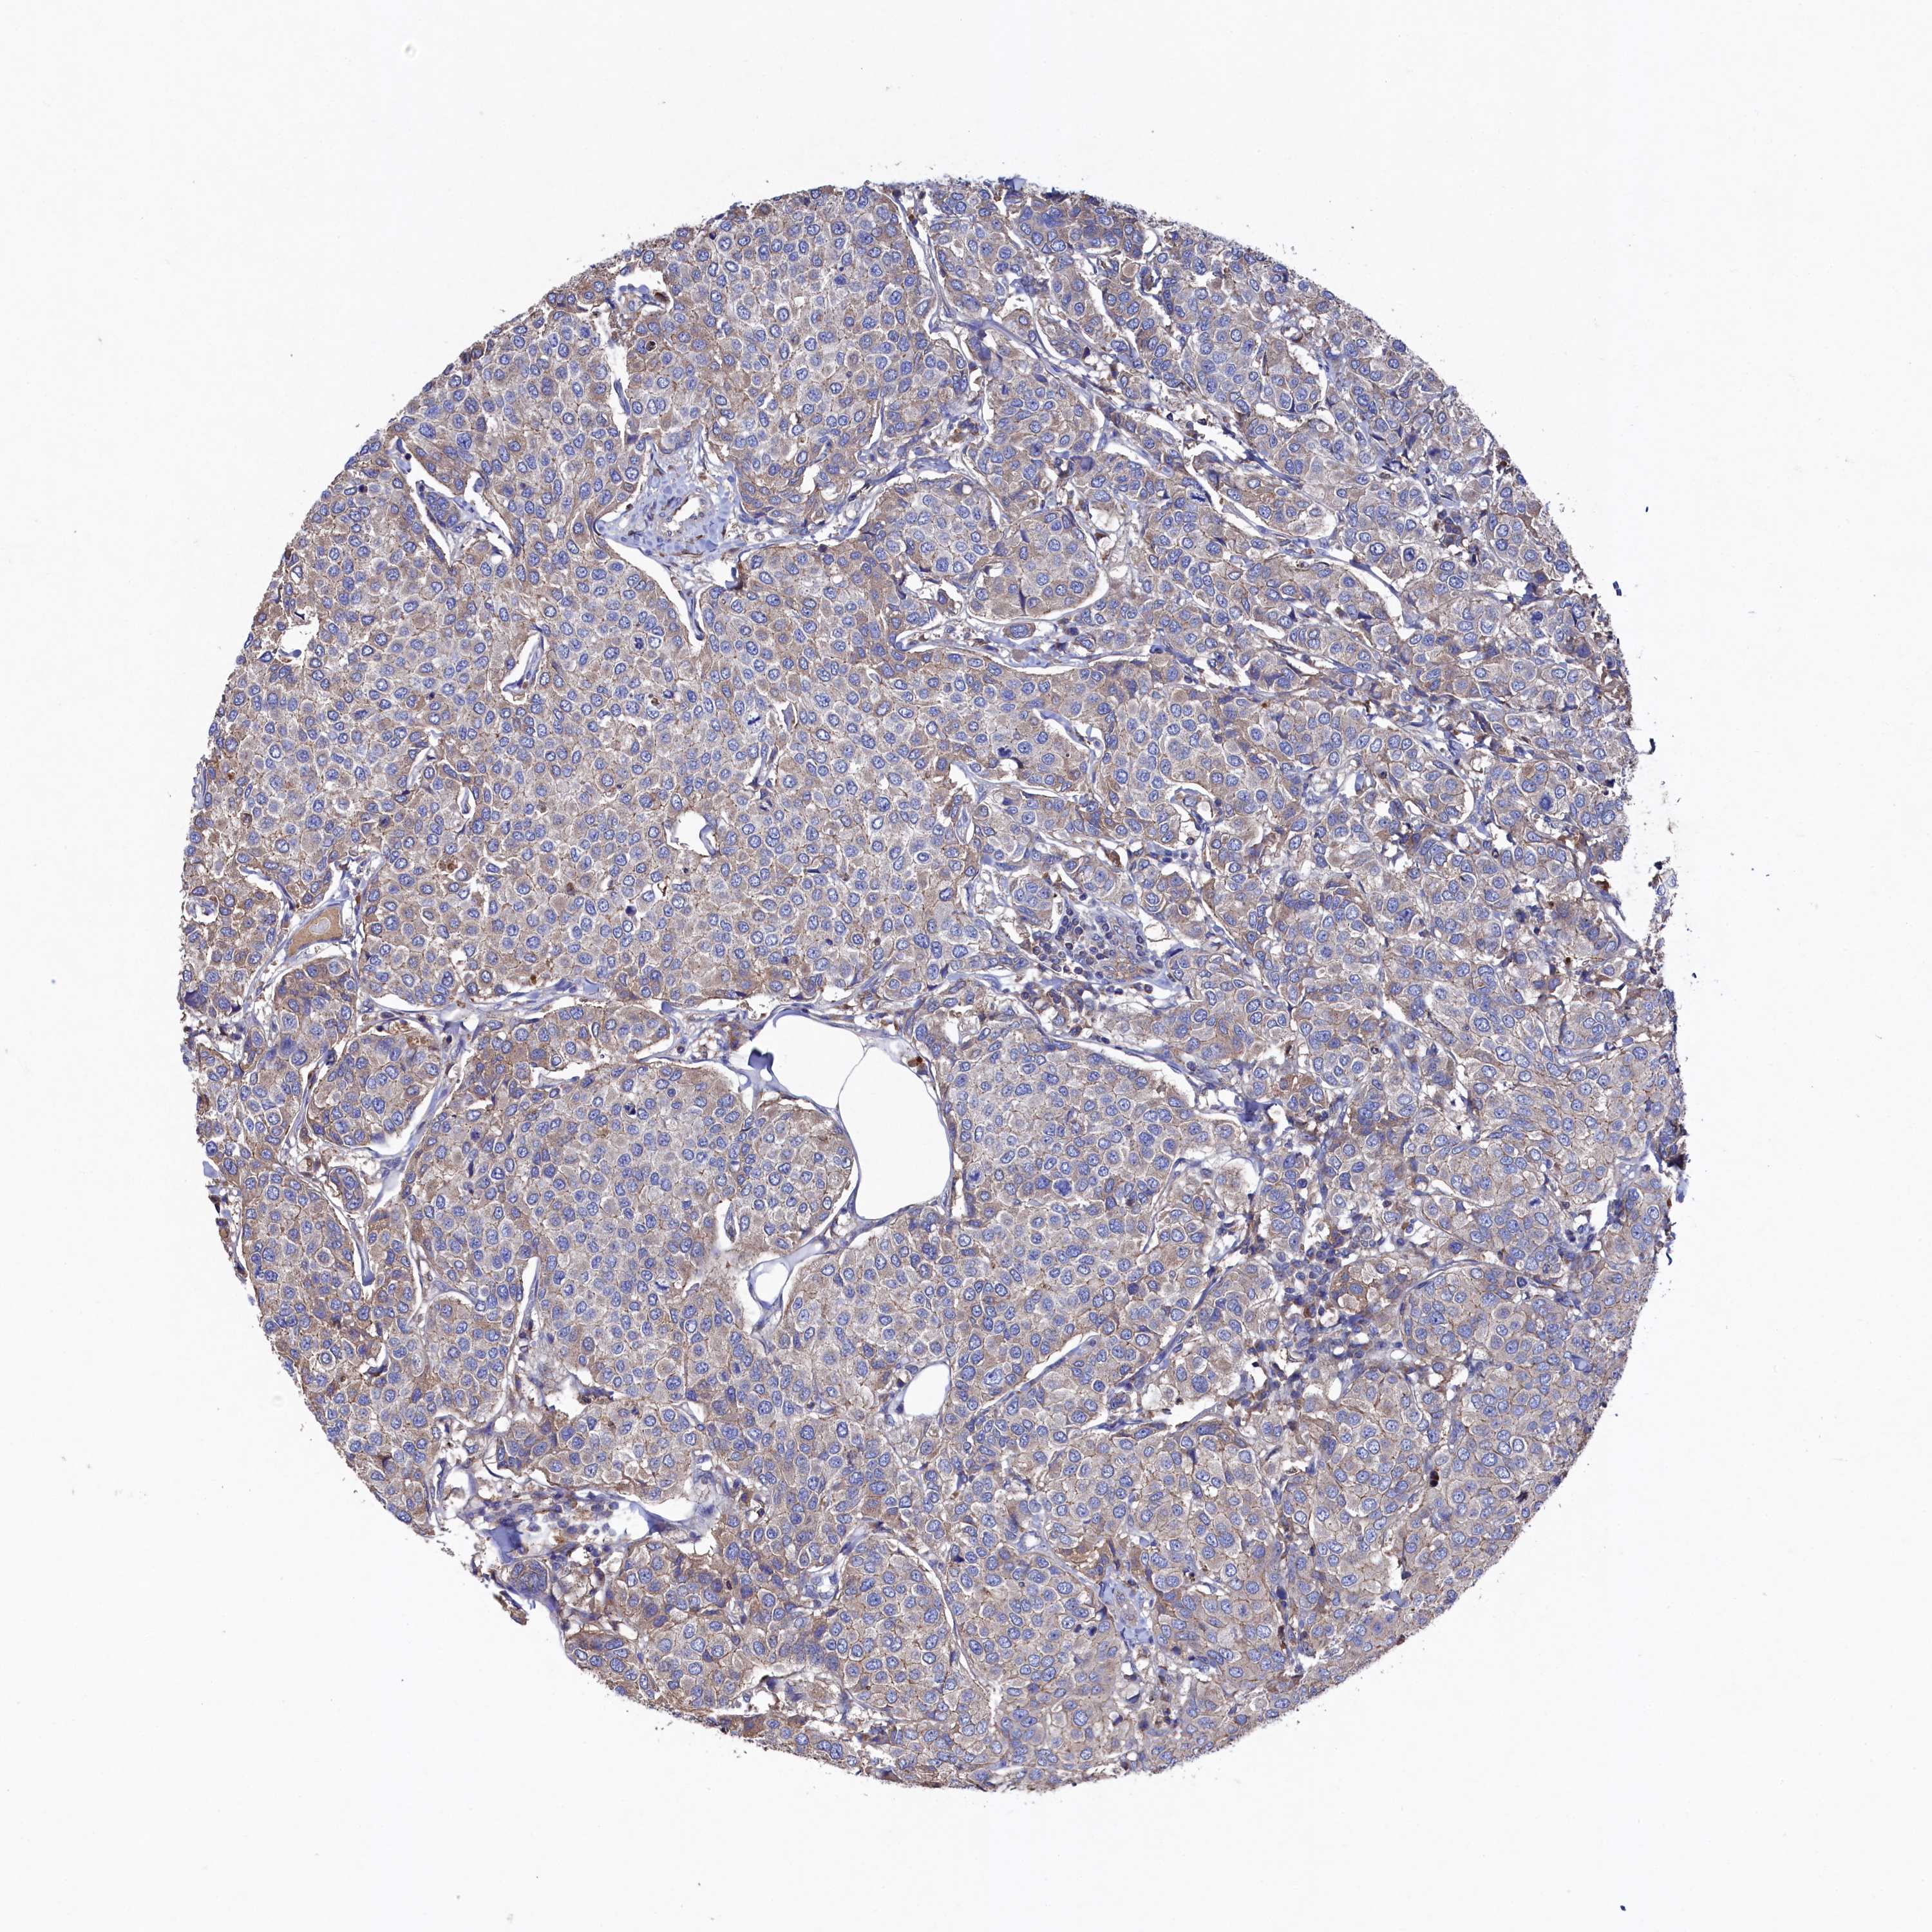

BRCA TCGA BRCA VALIDATION PROTEIN EXPRESSION

ANTIBODIES

AND

VALIDATION